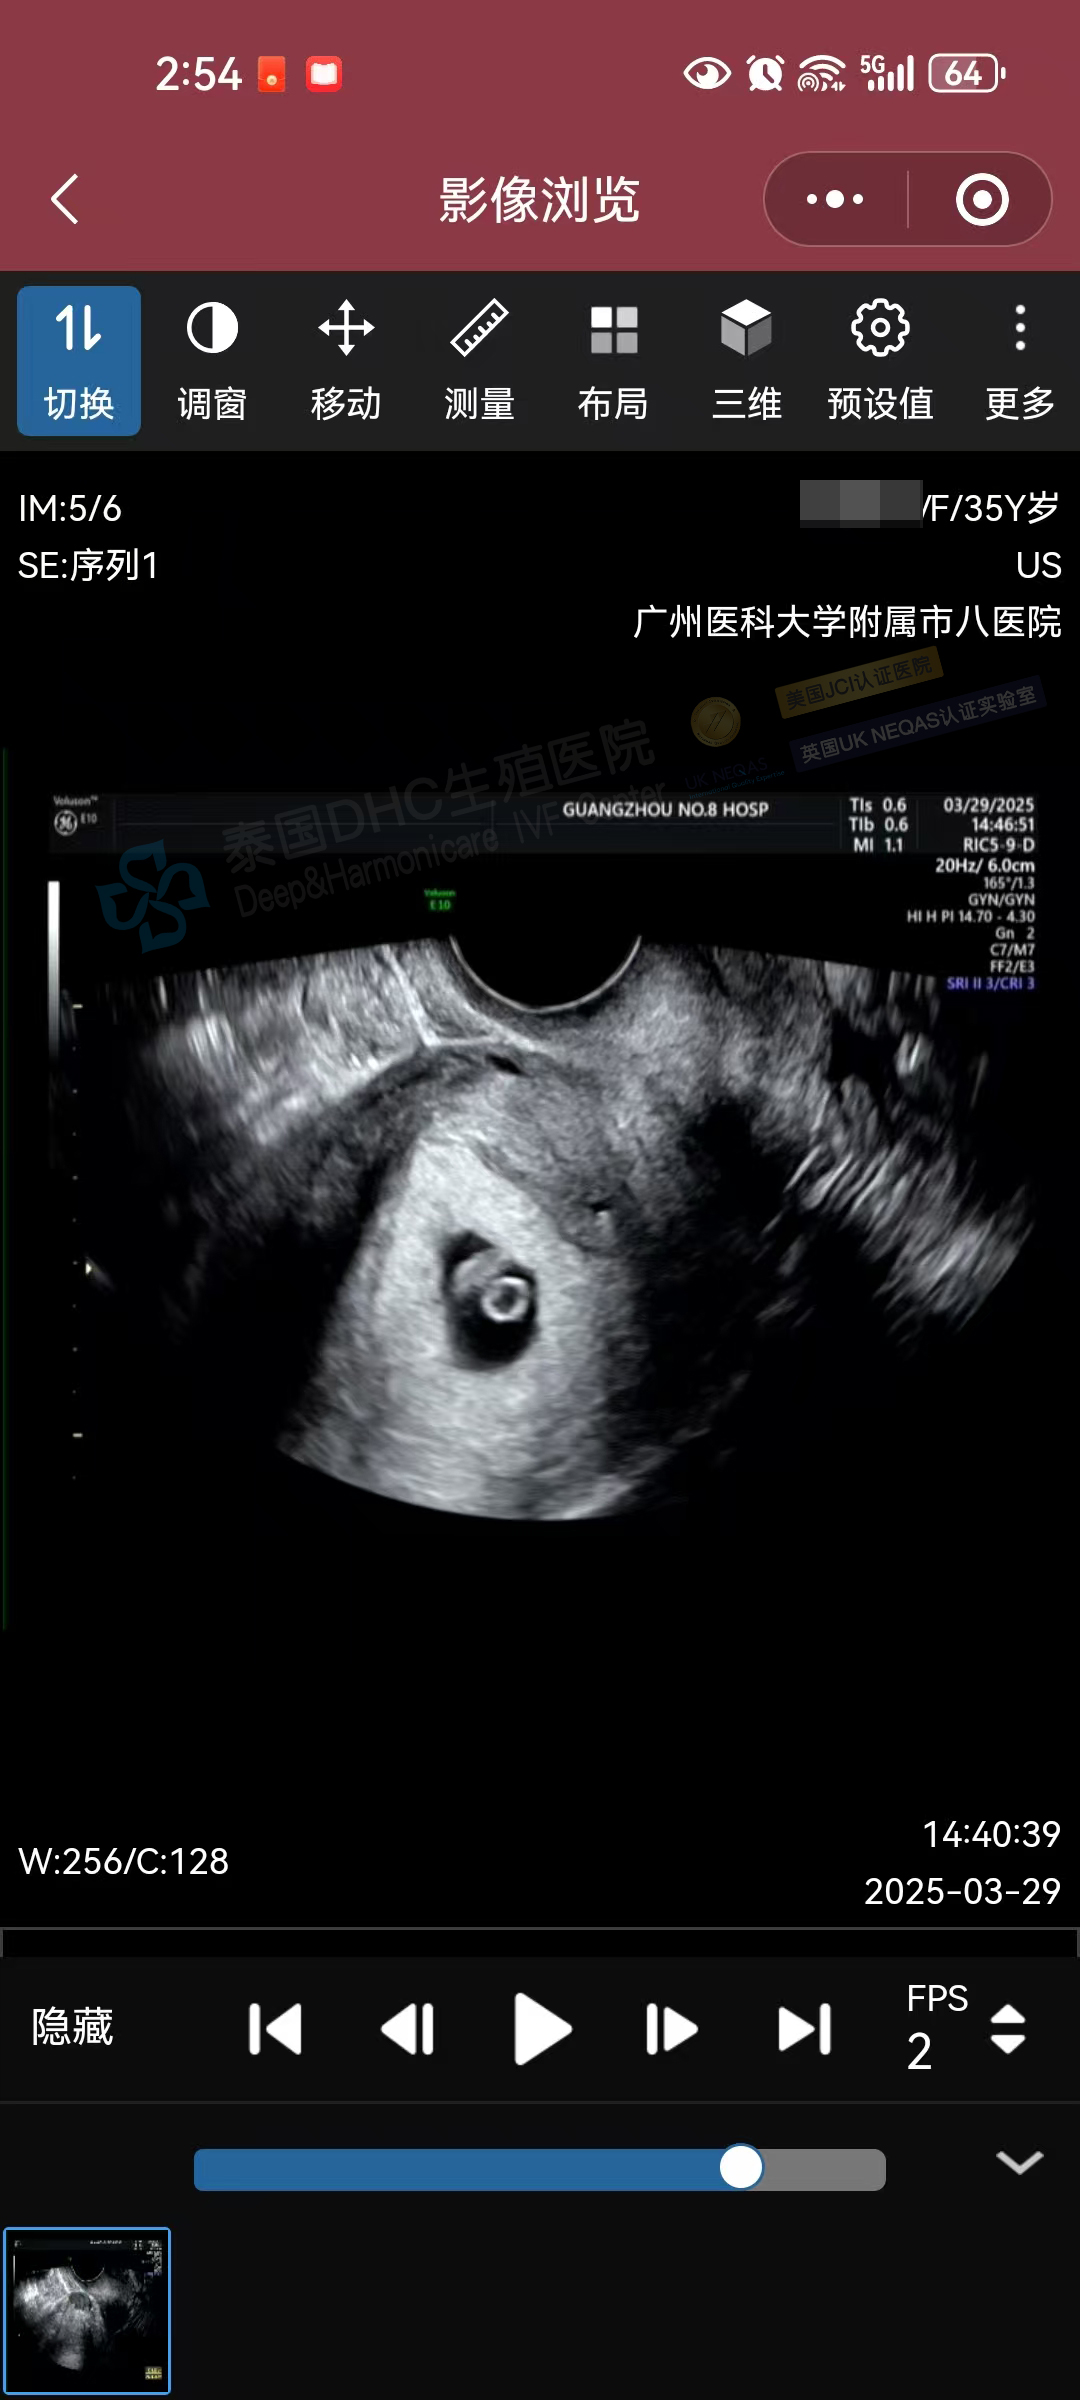

生命奇跡,如期而至!DHC三代試管助孕的35歲準(zhǔn)媽媽今日復(fù)查B超,再次迎來喜悅——小小寶貝胎心有力跳動,宣告著新生命的茁壯成長!?

大齡客戶優(yōu)選基因備孕二胎,在中泰一體化診療模式下,通過助孕寶+中西醫(yī)+營養(yǎng)師等綜合調(diào)精養(yǎng)卵助攻后,順利進(jìn)入試管周期,6枚囊胚篩查100%通關(guān)!恭喜客戶,科學(xué)備孕成功率棒棒噠。